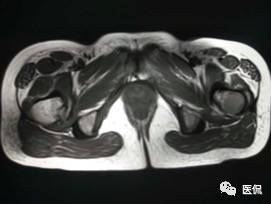

患者资料:男,26岁,左髋部疼痛10余天,无明显诱因出现左侧髋部疼痛,影像行走,夜间疼痛尤其明显。

影像资料:

(3)MRI ABC的特征为鼓囊状的膨胀性破坏,呈单囊或由低信号的间隔分隔成大小不等的多囊。因血细胞和血浆的分离和沉淀,囊内可见液-液平面。在T2WI上,液面上层为高信号,下层为低信号;T1WI上则相反,上层为低信号,下层为偏高信号。液-液平面是ABC较特征的征象。增强检查低信号的纤维间隔呈环形强化。继发性动脉瘤样骨囊肿可在其原发病灶内有液-液平。

【诊断要点】发生于青少年长骨干骺端偏心膨胀的溶骨性病变,MRI检查病灶内见有液-液平征象时应首先考虑为动脉瘤样骨囊肿。